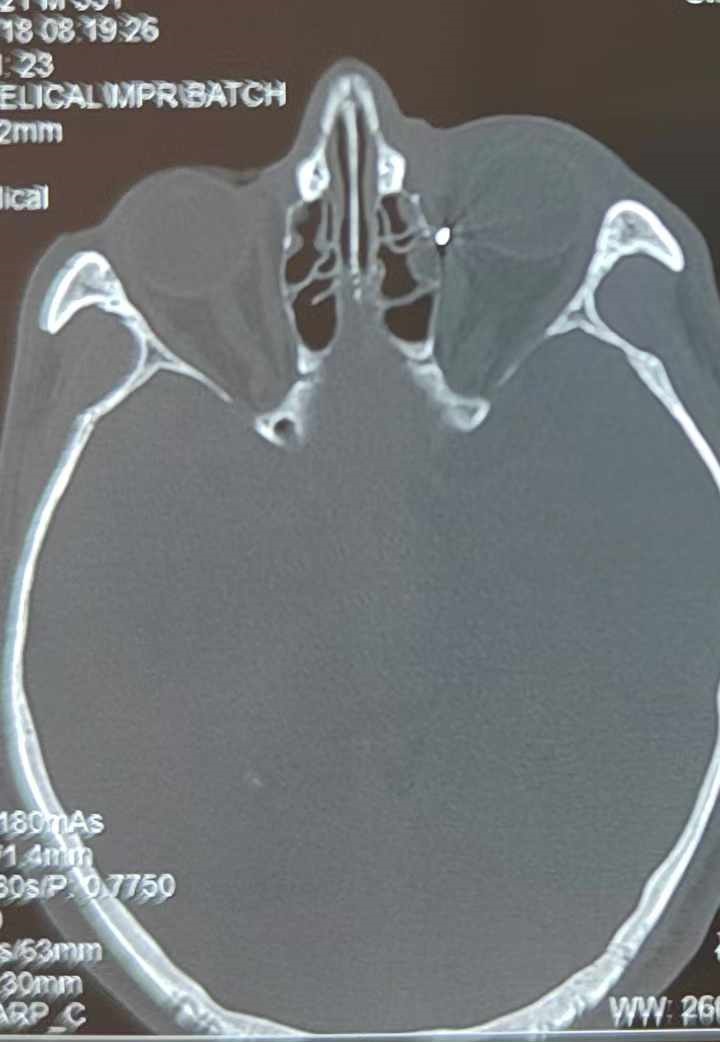

裝修工人高先生在作業(yè)過程中不慎被砸傷左眼,送至廈門眼科中心救治時,眼外傷及眼底病2科副主任醫(yī)師李海波博士在CT檢查報告中發(fā)現(xiàn),進入眼內(nèi)的異物在眶尖極為隱匿的位置,想要“不動聲色”地取出來,有些難度。

從CT報告中可以看出,高先生眼內(nèi)的異物不是很大,但位于眼窩深處,緊鄰鼻骨,從CT影像判斷應該是金屬或合金異物。一般臨床上遇到這樣的情況,醫(yī)生會建議“保守觀察”,若異物傷及神經(jīng)、發(fā)生炎癥感染等,則需到條件較好、有眼眶病和眼外傷專業(yè)醫(yī)師的醫(yī)院進行二期眶內(nèi)異物取出術(shù)(2021年《中國眼眶異物診斷和治療專家共識》)。

李海波博士介紹,眶內(nèi)異物想要通過手術(shù)取出,難度很大,一是因為位置隱匿,無法實現(xiàn)可視化操作;二是如果是磁性異物,現(xiàn)有手術(shù)工具磁性強度有限,很難吸出這么深的異物;三是可操作空間極為狹小,眶周軟組織多,異物周邊包裹緊密,像高先生這種情況,異物周邊還有很多神經(jīng)、血管,手術(shù)難度更高。